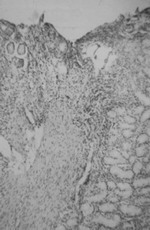

Գաստրիտի ակտիվությունը կախված է HP-ի տարածվածության աստիճանից։Ինչպես երևում է թիվ 2 աղյուսակից, առաջին աստիճանի ակտիվության գաստրիտ դիտվել էր 15 երեխաների մոտ։ Այս դեպքերում լորձաթաղանթը ծածկված էր լորձի բարակ շերտով, տեղ-տեղ այն պոկված էր, էպիթելիոցիտների մեծ մասը՝ հիդրոպիկ և լորձային սնուցախանգարման ենթարկված, հյուսվածքային կառուցվածքը՝ խանգարված։ Դիտվում էր փոսիկավզիկային և գեղձային էպիթելի բազմացում (նկ. 1)։

PAS - դրական ռեակցիա, X 400